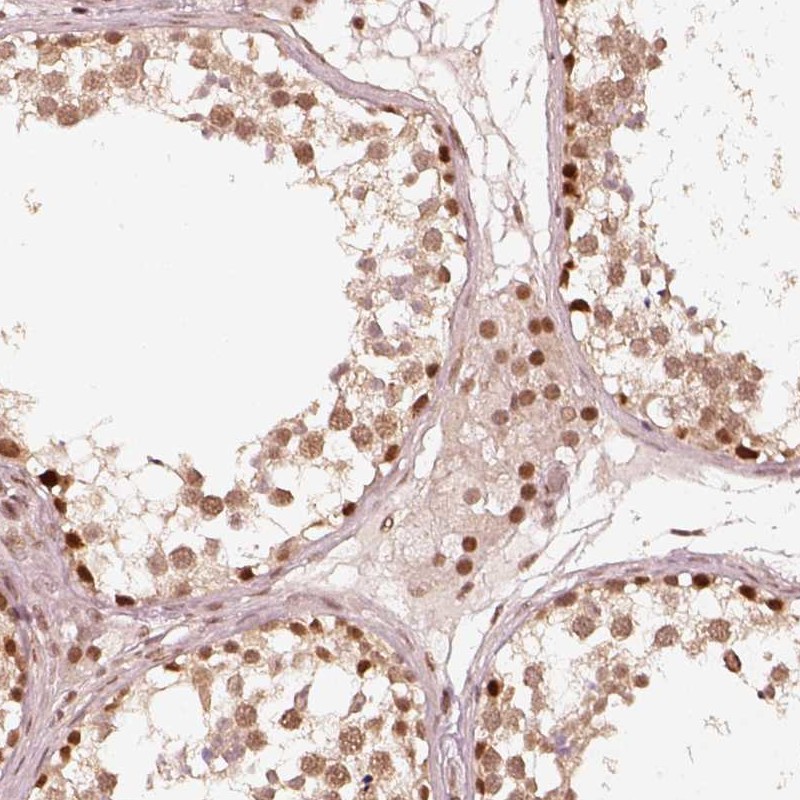

Immunohistochemical staining of human testis shows strong nuclear positivity in cells in seminiferous ducts and Leydig cells.